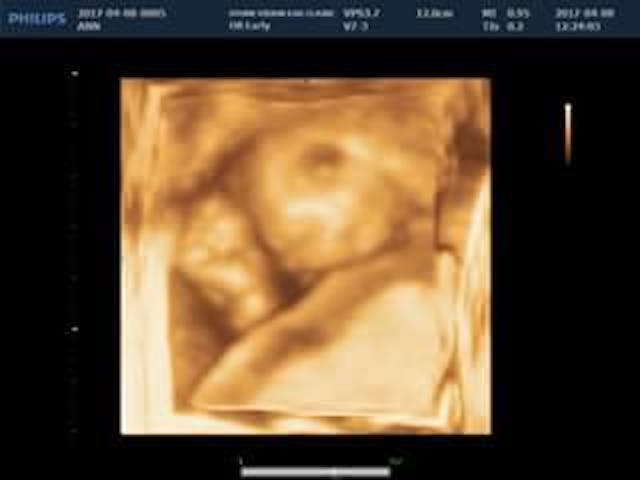

Already facing a high-risk pregnancy due to complete placenta previa, it was during a 14-week ultrasound that Ann Mahner first heard the word “anencephaly” used to describe her daughter. She had volunteered at the local pregnancy resource center two days earlier as a model for staff to practice on the new ultrasound machine. They could see that something wasn’t right, but without the doctor present, no diagnosis could be made.

Then, during the 20-week ultrasound, doctors found that the complete placenta previa had moved up and out of the way, which the Mahners call a complete miracle. The fear of rupturing and bleeding was gone; they wouldn’t have to deliver via C-section, and Miriam could arrive on her own schedule.